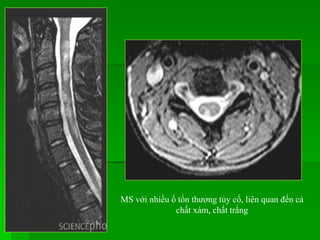

MS với nhiều ổ tổn thương tủy cổ, liên quan đến cả

chất xám, chất trắng

 Khởi phátbệnh từ 15-50 tuổi, nữ > nam.  Vị trí : - Gđ sớm bệnh ưu thế ở cột sống cổ, gđ sau bệnh phân bố như nhau ớ các đoạn. - Thường ở tủy sau bên và không tôn trọng ranh giới xám-trắng.  MRI: một hay nhiều tổn thương trong tủy giới hạn kém, kéo dài, tín hiệu thấp trên T1W, cao trên T2W, bắt Gd nếu ở gđ cấp. Tủy phình hay teo tùy tổn thương cấp hay mạn tính.  Khi lâm sàng nghi MS/ BN có bệnh lý tủy, nên chụp MRI não trước tiên, nếu bình thường thì nên chụp MRI xem tủy sống vì trong một số TH, tủy sống là nơi tổn thương sớm nhất. BỆNH MẤT MYELIN Bệnh xơ cứng rải rác

MS với nhiềuổ tổn thương tủy cổ, liên quan đến cả chất xám, chất trắng